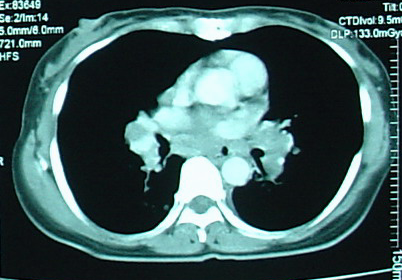

2. 血行播散性肺结核:急性血行播散性肺结核表现为两肺均匀分布的大小、密度一致的粟粒阴影;亚急性或慢性血行播散性肺结核的弥漫病灶,多分布于两肺的上中部,大小不一,密度不等,可有融合。需与电焊工尘肺、肺转移瘤等其他疾病鉴别。

*血行播散性肺结核:均匀分布的大小、密度一致的粟粒结节

*误诊为血播肺结核的电焊工尘肺,弥漫性肺病都必须询问职业史,无发热的血行播散性肺结核诊断需谨慎

*甲状腺癌肺转移:27 岁女性,双肺弥漫性粟粒影,误诊为血播,因无发热,质疑诊断,最后确诊为甲状腺癌肺转移。